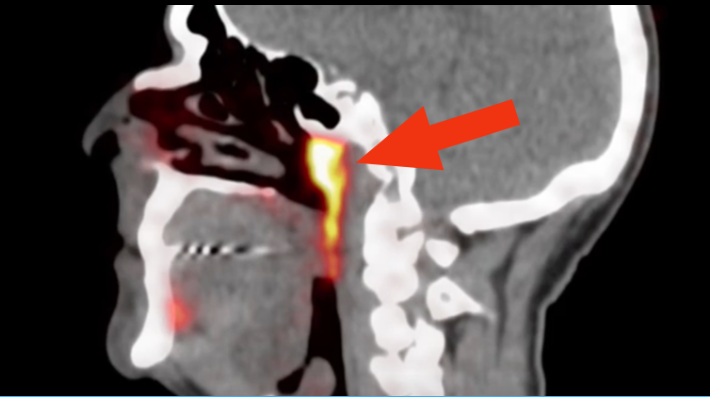

CT 장비를 이용해 한 암 환자를 스캔하는 과정에서 정말로 우연하게 발견된 건데요.

이 새로운 기관은 비인두(nasopharynx)라는 부위 뒤쪽 깊은 곳에 숨어 있었습니다.

이번의 발견에는 PSMA-PET / CT(전립선 특이 세포막 항원-양전자방출단층촬영)라는 완전히 새로운 기술이 이용되었는데요.

원래 이 장비는 전립선 암을 스캔하기 위해 개발된 장비입니다.

환자에게 특수한 포도당 주사를 주입한 뒤 이 장비로 스캔하게 되면, 몸에 있는 종양들이 뚜렷하게 보이게 되죠.

과학자들은 이 장비를 이용해 암 환자를 조사하는 과정에서 비인두 쪽에 숨겨져 있던 침샘을 우연히 발견하게 된 겁니다.